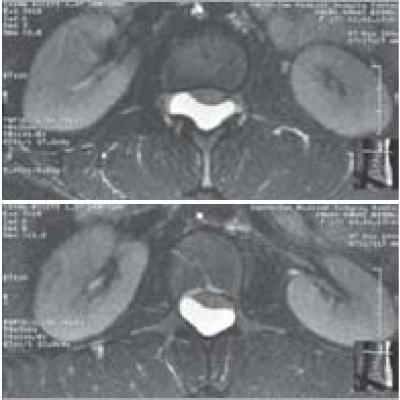

On MRI (Figures 1 and 2), arachnoid cyst was solitary in 12 cases. Only one patient presented 2lumbar arachnoid cysts. The location of the cyst was epidural in 11 cases and intramedullary in 2 cases. All the cysts were posterior or postero lateral. All cysts had cerebrospinal intensity on T1 and T2 weighted imaging.

Figure 1: arachnoid cyst.

Figure 2: The location of the cyst was epidural in 11 cases and intramedullary in 2 cases.